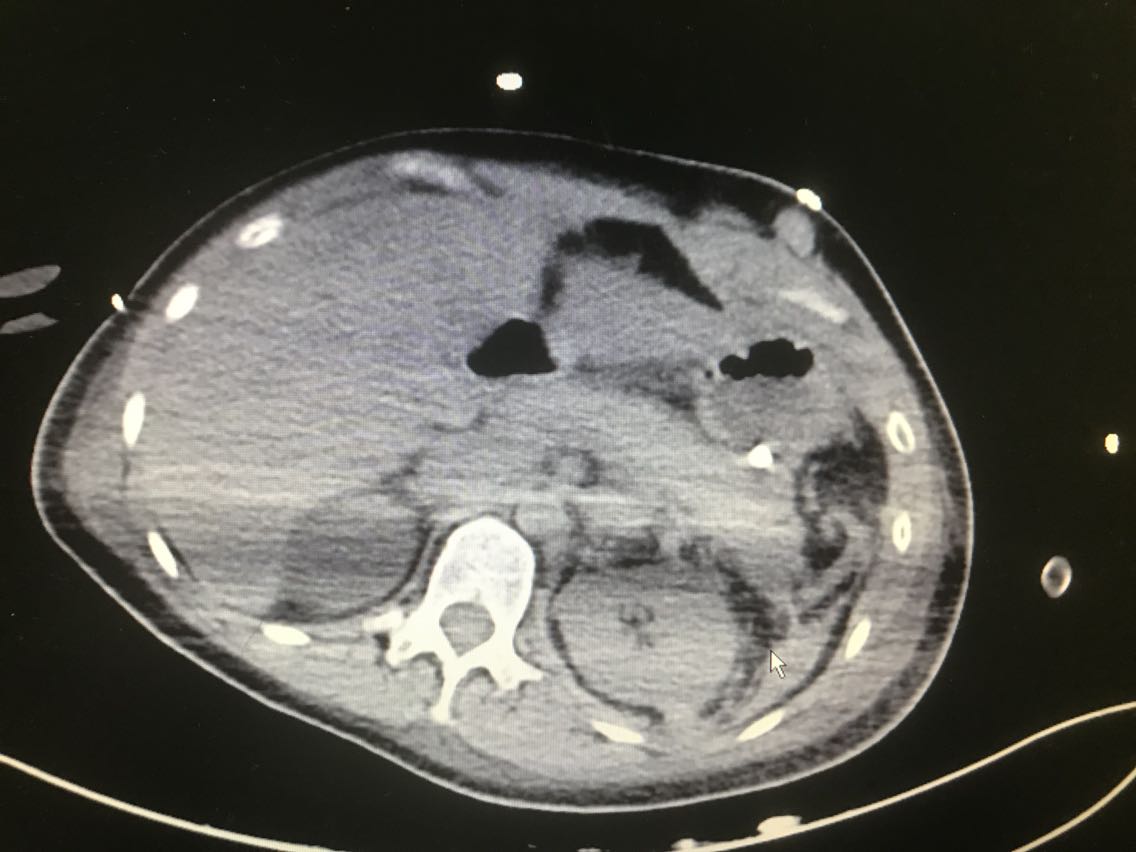

病史:55岁女性。患者自诉4年前在单位例行体检中行腹部超声检查提示“腹膜后肿瘤”,当时肿瘤较小(具体不详),未给予特殊处理,今年9月查腹部CT示“右侧腹膜后肿瘤(大小约70x45mm),左侧腹膜后腰大肌旁肿瘤(长径约22mm)”,收住入院。

辅查:CT平扫+增强扫描示:右侧膈下肾上腺区和左侧腰大肌病灶, 考虑为良性肿瘤,嗜铬细胞瘤可能性大,未除外其他

讨论:该例嗜铬细胞瘤具有较典型的影像表现,我们能看到右侧肾上腺椭圆形肿块,边界清楚,直径较大,这可区别于肾上腺腺瘤,后者一般小于2cm。增强扫描肿块明显强化,并可见无强化低密度区,可能是肿瘤常坏死或陈旧性出血引起。而且该患者有嗜铬细胞瘤引起的继发性高血压,不过追问病史没有典型的阵发性高血压发作。